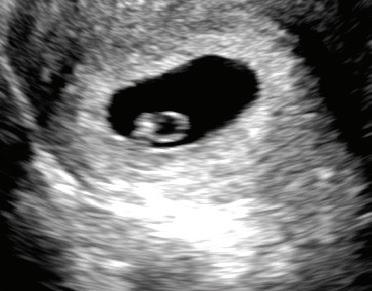

6 WEEKS LMP

The embryo’s heart activity can be seen during an ultrasound. The brain is dividing into its three main parts.3